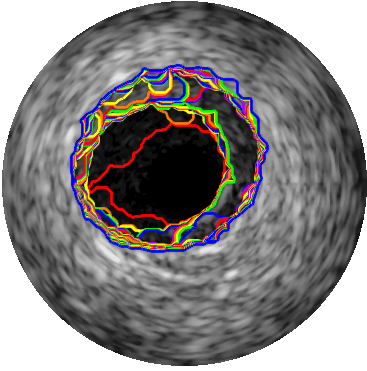

3.3 EREL Selection Results

Qualitative evaluations are illustrated in Figure 4 and show the successful segmentation results of the proposed EREL selection strategy for 20 IVUS frames. The lumen areas are highlighted by the magenta colour while the media regions are green. Also, the manually annotated contours for both lumen and media are drawn as yellow dashed lines. As we can see, the chosen frames contain a variety of lumen and media morphologies.

A detailed evaluation result and comparison with 9 recently published IVUS segmentation methods are reported in Table 3 where the performance of the proposed EREL selection strategy in the presence of various artifacts is shown as well.

Secondly, we propose an ERELs selection strategy based on creating a vector that represents several textural characteristics of the regions and search for the regions which have higher textural stability scores. This method works very well when no artifact is present in the IVUS image or more accurately, when no major artifact is attached to the media. In this case, the average Hausdorff distance for both lumen and media is less than mm which shows that the proposed method works very well for images without any strong artifact. Furthermore, the general performance of our proposed method for lumen segmentation is superior to other available methods in terms of the average Hausdorff distance, which is mm. Likewise, our method is able to segment the lumen when the image contains shadows ( mm) or side vessel ( mm) artifacts, which is by far the lowest distance to the gold standard.

If artifacts that are usually dark (low intensity value) regions, join the lumen and media regions, a type of leak will be created. This leak significantly increases the size and the mean intensity of the regions and generates irregular patterns that are very difficult to distinguish by the EREL extraction algorithm. Some of the inaccurate segmentations that are caused by the presence of the artifacts are shown in Figure 5. As can be seen in Figure 5, although the presence of the artifacts disrupts the detection of the media regions, most of the lumen regions can still be segmented accurately. This is also supported by the quantitative results presented in Table 3. Evidently, even in the presence of artifacts such as bifurcations, side vessels, and shadows, the lumen segmentation performance remains high, though the accuracy of the media segmentation drops. In fact, even in the worst case condition of lumen segmentation that happens when the image contains bifurcation artifacts, the average Hausdorff distance to the gold standard is only mm which is still lower than most of the other methods. On the other hand, the media segmentation is more sensitive to the presence of artifacts. For instance, the Hausdorff metric for media in some cases increases to mm for bifurcation and to mm for shadow artifact. Accordingly, it can be concluded that the lumen segmentation is robust to the common artifacts of the IVUS images.